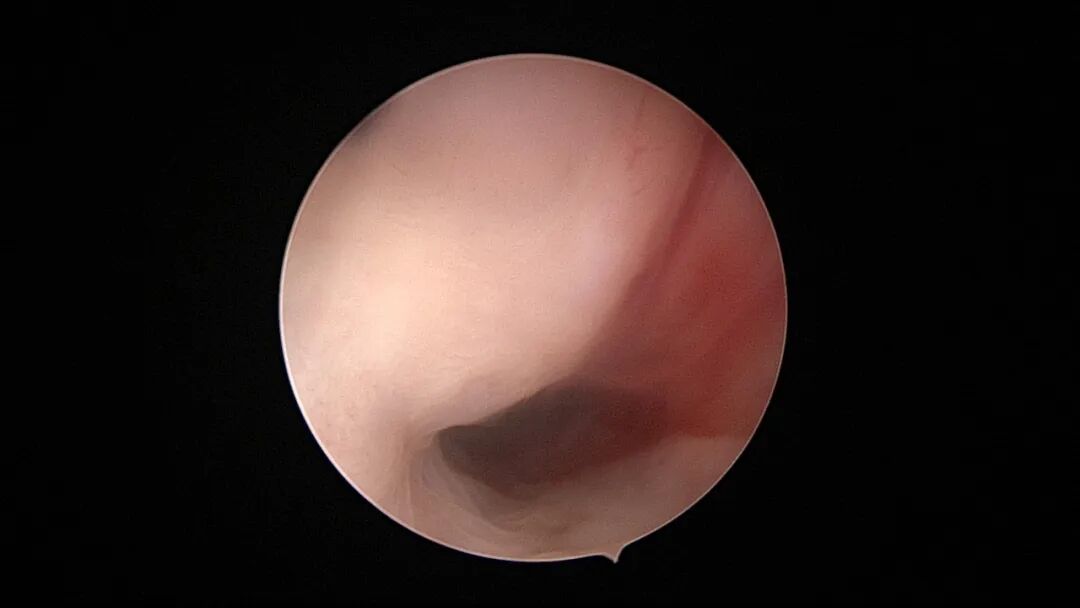

第一次宫腔镜:2021年4月,闭经50+天,B超提示宫腔粘连,宫腔镜探查见宫颈管上段封闭粘连,宫腔广泛粘连,AFS评12分(最高分)。宫腔镜单极电切分粘,恢复宫腔形态,显露双侧输卵管开口,右侧宫角附近内膜柔软、红润,宫腔防粘连复发处理。